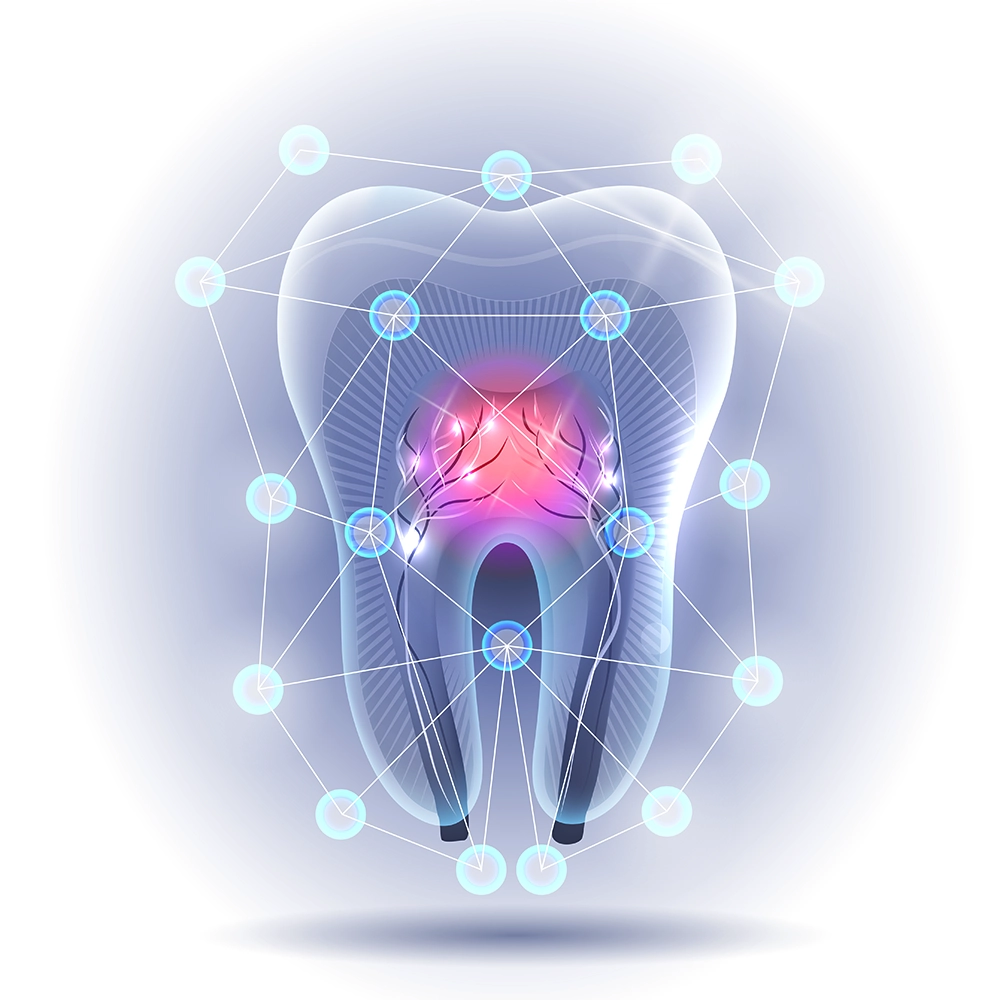

3D illustration showing a detailed cross-section of a tooth with highlighted areas showing nerves and blood supply within the tooth structure.

Relief from Pain

Root canals often get a bad rap for being painful, but they are actually the solution to pain, not the cause. Persistent tooth pain, swelling, or an abscess can indicate the need for this treatment. We’re here to turn that discomfort into relief, providing advanced care to restore your oral health.